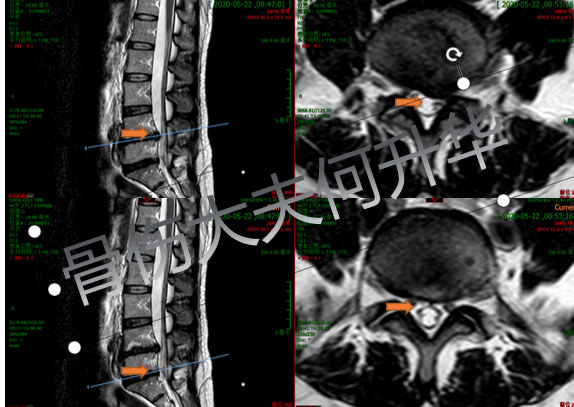

入院后,CT橫斷面片顯示腰部左側(cè)4/5

椎間盤突出癥、腰椎4型椎體終板炎癥表現(xiàn)

入院后MRI橫斷面片顯示腰椎左側(cè)4/5

椎間盤突出癥,腰椎 5 骶骨 1 椎間高度下降